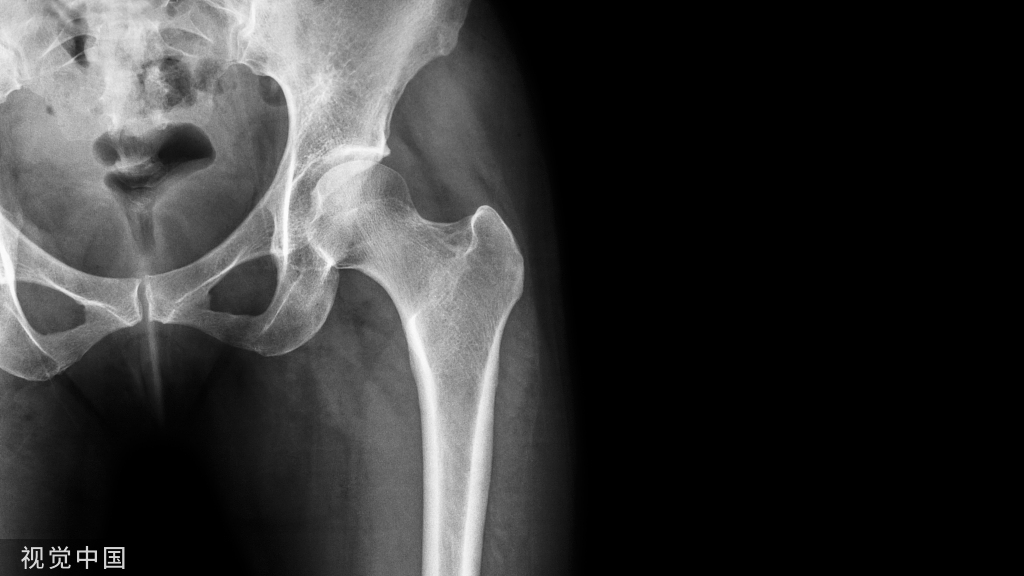

半夜来了这两个病人我都需要急诊手术吗?

现在来了两个开放骨折,一个前臂,一个距骨,我应该怎么处理?什么时候我需要急诊手术呢?开放骨折、肢体毁损、没有动脉搏动、多发伤患者一个放开骨折来了我需要做什么呢?